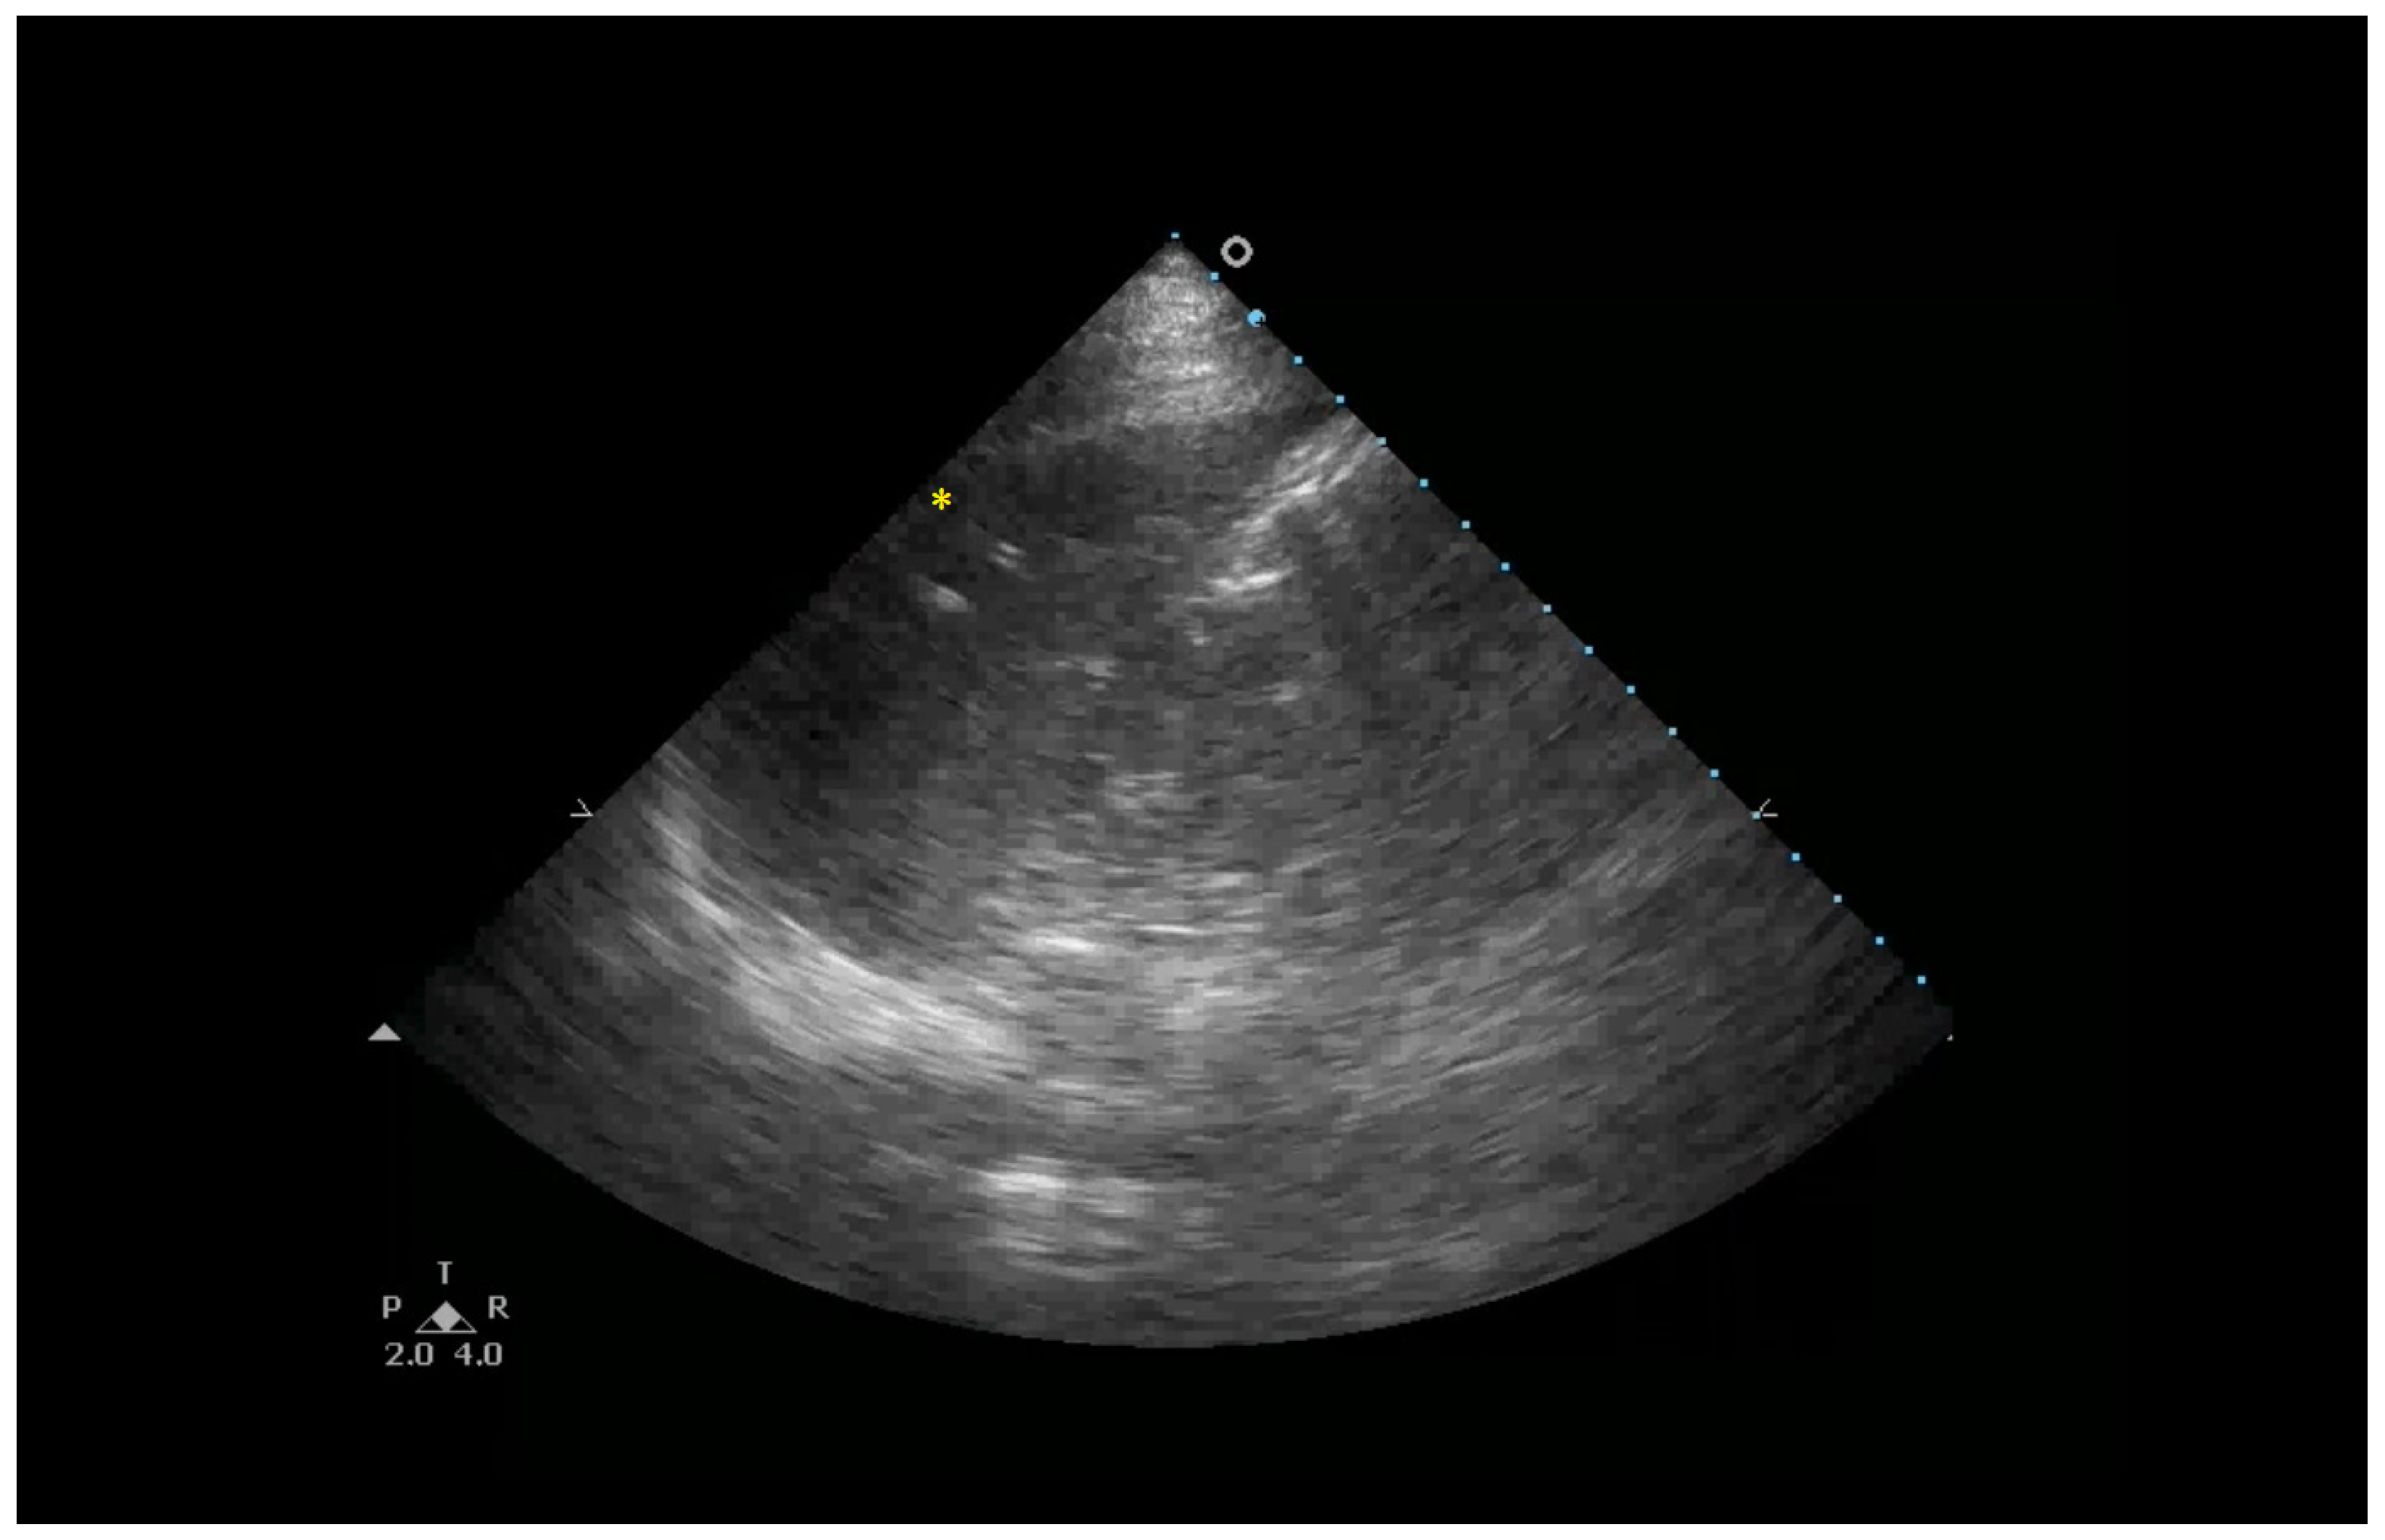

6.1. Sonographic Findings

- Anterior subpleural consolidations;

- Absent or reduced lung sliding;

- “Preserved areas” of normal lung parenchyma;

- Abnormalities in the pleural line (e.g., fragmented, thickened, or irregular pleural line);

- Inhomogeneous distribution of B-lines.